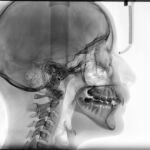

Un examen de tomografía computarizada (TAC) macizofacial es una herramienta diagnóstica esencial en la…

El examen de TAC macizofacial, o tomografía axial computarizada macizofacial, es una técnica de…